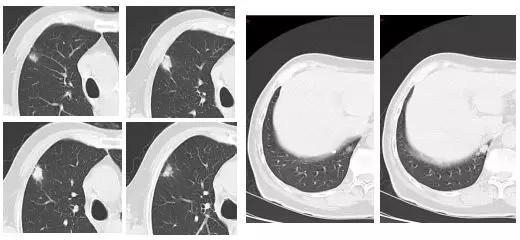

患者基本资料:王某,男性,70岁,2017年4月27日体检时发现双肺占位。查体时无阳性体征。PS评分1分。体检时的肺CT:肺窗显示双肺见多发、散在、大小不一的实性结节。纵隔窗显示病灶呈实性结节,见分叶征,边缘毛糙,瘤肺界面清楚。

图一:2017.4.27体检时肺CT